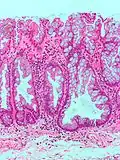

Hyperplastic polyp | Colorectal (unless otherwise specified) | Serrated unbranched crypts | if polyps are more than 100 | ![]() |

Serrated polyposis syndrome |